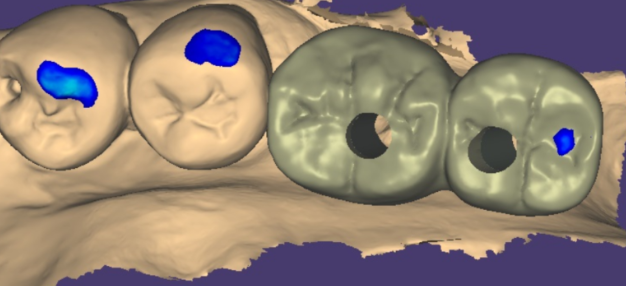

231221

임플란트와 내 뼈가 충분히 붙으면

기둥을 끼우고 보철물을 만들어줍니다.

스캔 기계를 사용하여 뽄을 뜨고 보철을 만들어줍니다.